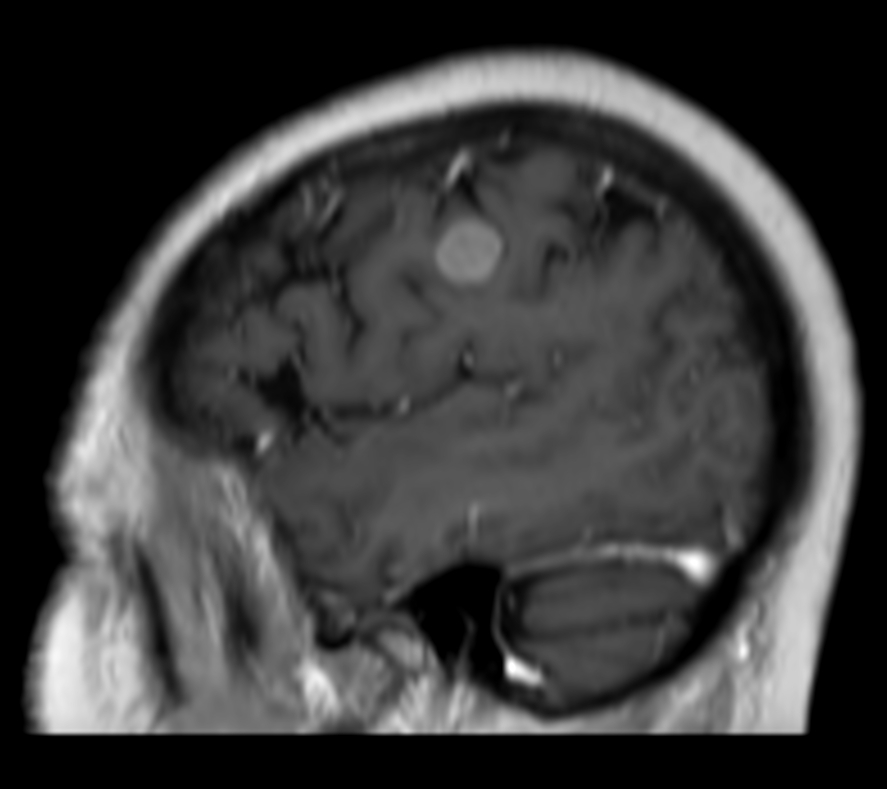

Female with one metastasis of pulmonary cancer underwent MRI simulation in the radiotherapy positioning mask on Ingenia MR-RT 1.5T before stereotactic radiation therapy with 25 Gy in 3 fractions.

3D T1w FFE (sagittal reformat) post contrast